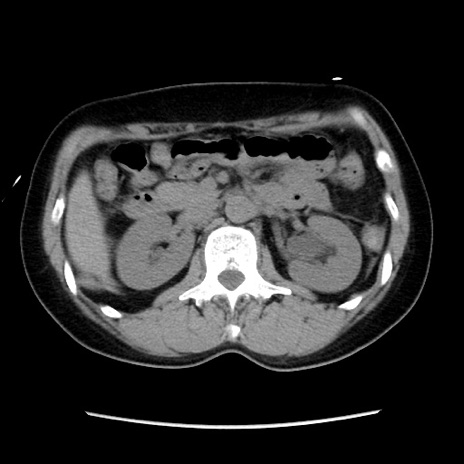

冠状断像